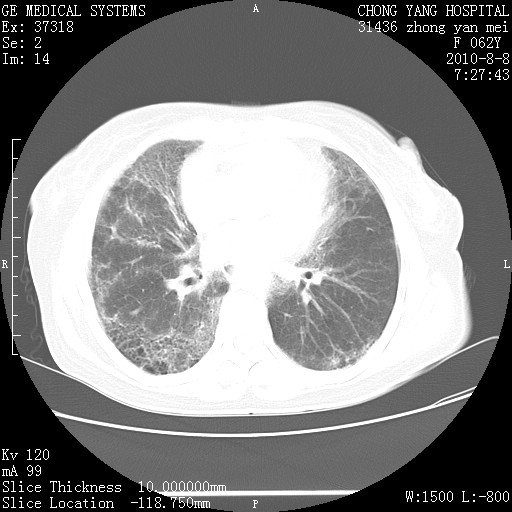

标题: CT28269:F62Y咳嗽胸痛数月。 [打印本页]

标题: CT28269:F62Y咳嗽胸痛数月。

两肺弥漫性间质纤维化伴继发性支扩。

考虑特发性肺间质纤维化

考虑两肺间质性肺炎并肺间质纤维化。

双肺间质纤维化合并感染、肺气肿

两肺间质纤维化并牵拉性细支气管扩张。

考虑两肺间质性肺炎并肺间质纤维化,肺气囊形成。

两肺间质改变,纵隔淋巴结肿大,需要考虑结节病的可能。